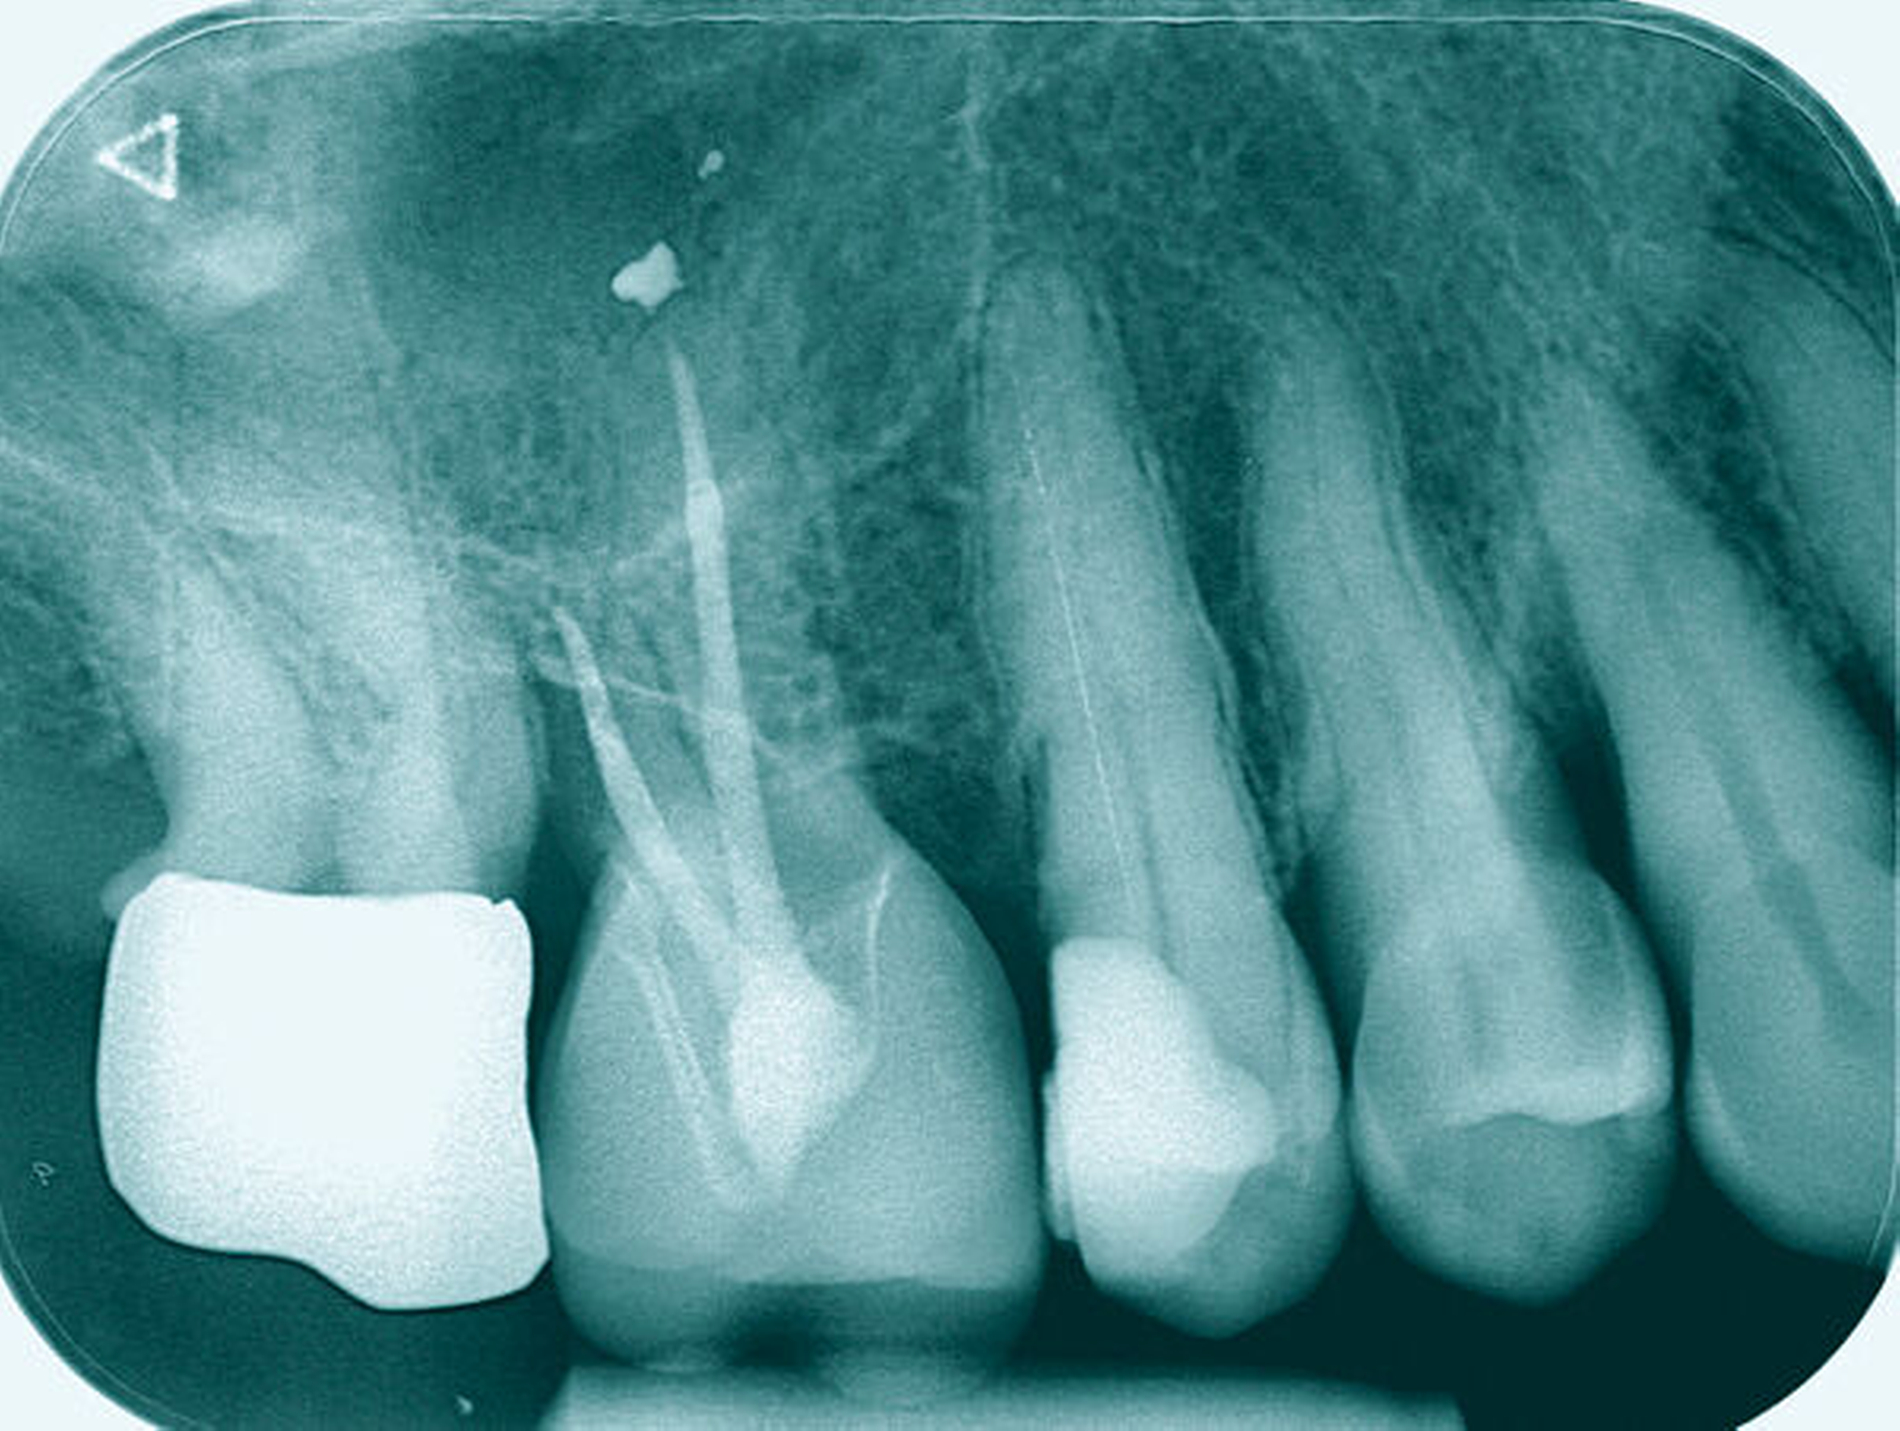

Um sicherzustellen, dass der Zahn für das gewählte Vorgehen geeignet ist, erfolgt zunächst die Auswertung der vorliegenden Röntgenbilder, eine ausführliche parodontale Sondierung des Zahnes mit Parodontalsonde und Nabers-Sonde, um Attachment und Furkationsbefall sowie möglicherweise tastbare anatomische Besonderheiten zu beurteilen. Das Röntgenbild besitzt zwar eine nur eingeschränkte Aussagekraft bezüglich des interradikulären Knochenangebots [Eickholz, 2010; Topoll et al., 1988], das durch das DVT besser beurteilbar zu sein scheint [Walter et al., 2010], jedoch waren die in diesem Beitrag gezeigten Fälle durch die Kombination aus klinischer und röntgenologischer Diagnostik ausreichend beurteilbar, um eine Therapieplanung ohne DVT durchzuführen.

Eine 54-jährige Patientin stellte sich 2018 in der Praxis vor, nachdem sie beim Essen ein Goldinlay an Zahn 16 verloren hatte. Sie klagte über eine Aufbissempfindlichkeit des Zahnes sowie über das Gefühl einer Lockerung. Klinisch zeigte sich eine tiefe Fraktur des Zahnes in mesiodistaler Richtung. Nach klinischer und röntgenologischer Diagnostik wurde die Patientin über die Möglichkeit der Extraktion mit anschließender prothetischer Versorgung der Lücke und den aufwendigen Erhaltungsversuch mittels endodontischer Behandlung des Zahnes samt Amputation der palatinalen Wurzel aufgeklärt. Die Patientin war sehr motiviert und entschied sich für den Erhaltungsversuch.

So erfolgte nach endodontischer Behandlung des Zahnes die Amputation der palatinalen Wurzel und die Versorgung des Zahnes mit einer Vollkrone. Die Situation an 16 ist seitdem stabil, allerdings zeigen sich auch hier palatinal erhöhte Sondierungstiefen, die röntgenologisch mit einem progredienten Knochenabbau im Bereich der Furkation zu korrelieren scheinen. Die Patientin gibt an, mit der Reinigung des Zahnes keine Probleme zu haben, möglicherweise ist diese jedoch durch die Einziehung im Bereich der Furkation vor allem palatinal erschwert. Die Patientin wurde daraufhin instruiert, wie sie die häusliche Mundhygiene in den schwer zugänglichen Bereichen intensivieren und verbessern kann.